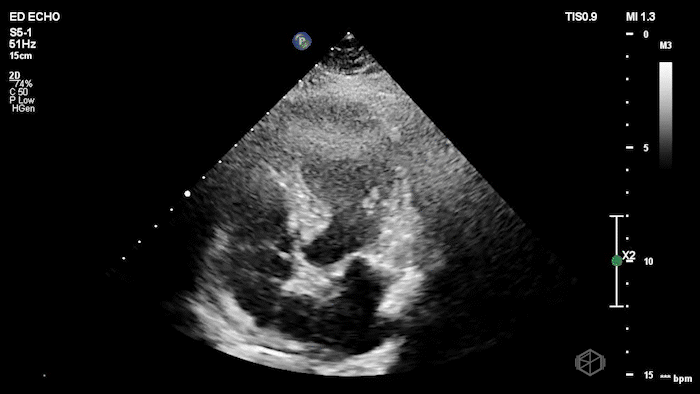

The next SonoProps goes to Dr. Andrew Weinberger. He performed a scan on a mid-70’s female with a past medical history of hypertension, diabetes, hyperlipidemia that had neck pain and then started having chest pain.

His scan showed the following:

The echo shows a reduced ejection fraction with an antero-septal wall motion abnormality.

The patient’s EKG demonstrated an antero-septal AMI.

The patient was taken for a cath and found to have a 100% LAD occlusion. The ejection fraction was 20-29%.

Diagnosis: AMI - Anteroseptal LAD 100%

RWMA shows up early and maps the culprit. In acute ischemia, new regional wall-motion abnormality (RWMA) appears before—or despite nondiagnostic—ECG changes. In STEMI cohorts, EM residents with core ultrasound training detected RWMAs with sens 88% / spec 92% vs comprehensive echo, and territory agreement was substantial—useful for rapidly localizing an LAD-territory infarct like this case. (📚 PMID: 30987914)

High specificity helps you “rule-in” in non-ST presentations, but don’t “rule-out” with a normal scan. In ED chest-pain patients without ST-elevation, POCUS-detected RWMA predicted NSTE-ACS with spec ~93% but sens ~43%—great when present, insufficient to exclude ACS when absent. Treat a normal study as low likelihood, not a discharge ticket (📚 PMID: 38985842).

Residents and EM attendings can learn this and perform well. A 30-minute teaching module improved EP accuracy for WMA recognition from 67% → 87% on test images (pre/post). In clinical ACS cases, residents achieved sens ~86% and attendings/fellows ~85% for RWMA vs cardiology echo (specificity higher in more experienced operators). (📚 PMID: 22046540)

When new RWMA is seen by EPs in patients who don’t meet initial ECG cath-activation criteria, it closely matches cardiology echo findings (EP RWMA vs cardiology echo: spec 96%) and is highly specific for patients who will undergo intervention/CABG (spec ~93%, sensitivity modest). Use ‘new RWMA’—relative to a prior normal echo—as a trigger for expedited cardiology involvement. (📚 PMID: 38205979)

Common pitfalls: Old infarcts/cardiomyopathy can mimic “new” RWMA; paced rhythms/LBBB can confound ECG, making echo relatively more helpful. Suboptimal windows and tachycardia can hide subtle hypokinesis—optimize gain, depth, and frame-by-frame endocardial tracking; when in doubt, label as “possible RWMA—needs cardiology echo.”